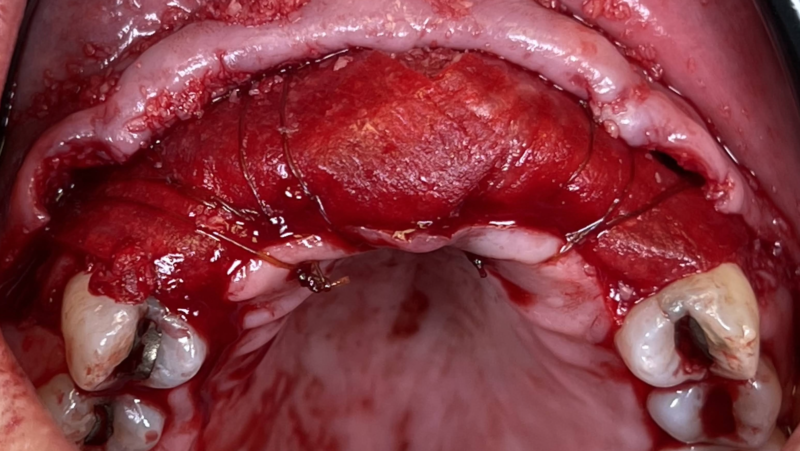

Ivan posted an update 2 years ago

I want to share a case I’m particularly proud of. My homie AJ Marbeh in San Diego took this case from start to finish. After taking the online GBR course by David Wong he crushed it with this difficult case and he used Implant Club fixtures. Brings a tear of happiness to my eye. LOL but seriously, Love this case!